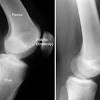

There are bursa located underneath the tendons and ligaments on both the lateral and medial sides of the knee.

The hamstring muscles are flexors, moving the upper leg (femur). Items similar to 1905 leg muscles tendons u0026 ligaments. Ballistic stretches are quick movements that bring your muscle into a stretch and then are quickly released. Each muscle of this group starts at four different locations on the femur and pelvis, and the muscles merge into one common tendon (tendon of quadriceps) between the tendons is a space called the popliteal fossa, with a small fat pad. Tendons and ligaments also provide an elastic response, a. Because these muscles and tendons get so much use, it is very easy for them to get overworked and tight. The muscles of the thigh and lower leg are comprised of compartments defined as distinct anatomical spaces bordered by fascia or bone. Section editor dean taylor, md. Books on muscles and tendons. Katelyn forsee how do our muscles work? There are bursa located underneath the tendons and ligaments on both the lateral and medial sides of the knee. Proper care to be taken to prevent them from injuries. Tendons and muscles are an example of this.